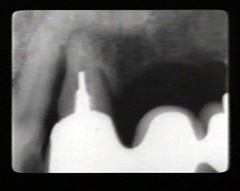

Las radiografías periapicales muestran pérdida de hueso alveolar en aproximadamente la mitad de la longitud de la raíz. La pérdida de hueso en el área de furacación se indica por la radiolucidez aumentada en la unión de las raíces en la región cervical.

Los premolars han perdido más de la la mitad de la longitud de la raíz del hueso alveolar periodontal.  Hay defectos infraóseos en particular en el segumdo premolar en mesial y distal. El modelo semilunar que cubre la raíz del segundo premolar también indica la presencia de una defecto óseo en palatino.